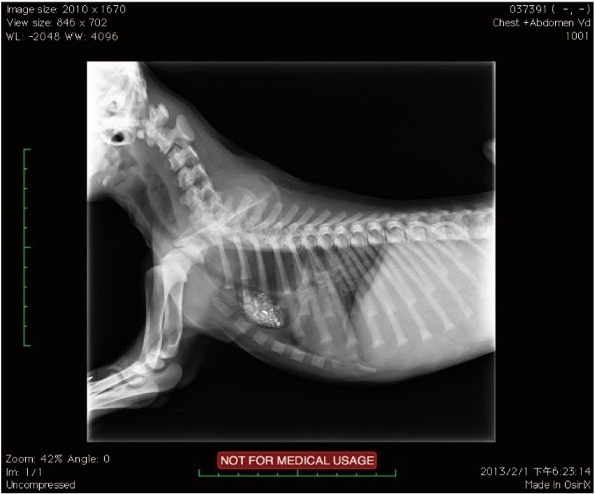

發病年齡,往往都在二到三個月大,通常都是長時間的慢性嘔吐、極度消瘦丶極度飢餓來醫院就診,x光是最好的診斷工具,除了明顕的食道擴張(心基部之前),常常可以發現吸入性肺炎的胸腔影像。

【圖十一】兩個月大的米克斯幼犬, x光下發現食道在心基部之前擴張